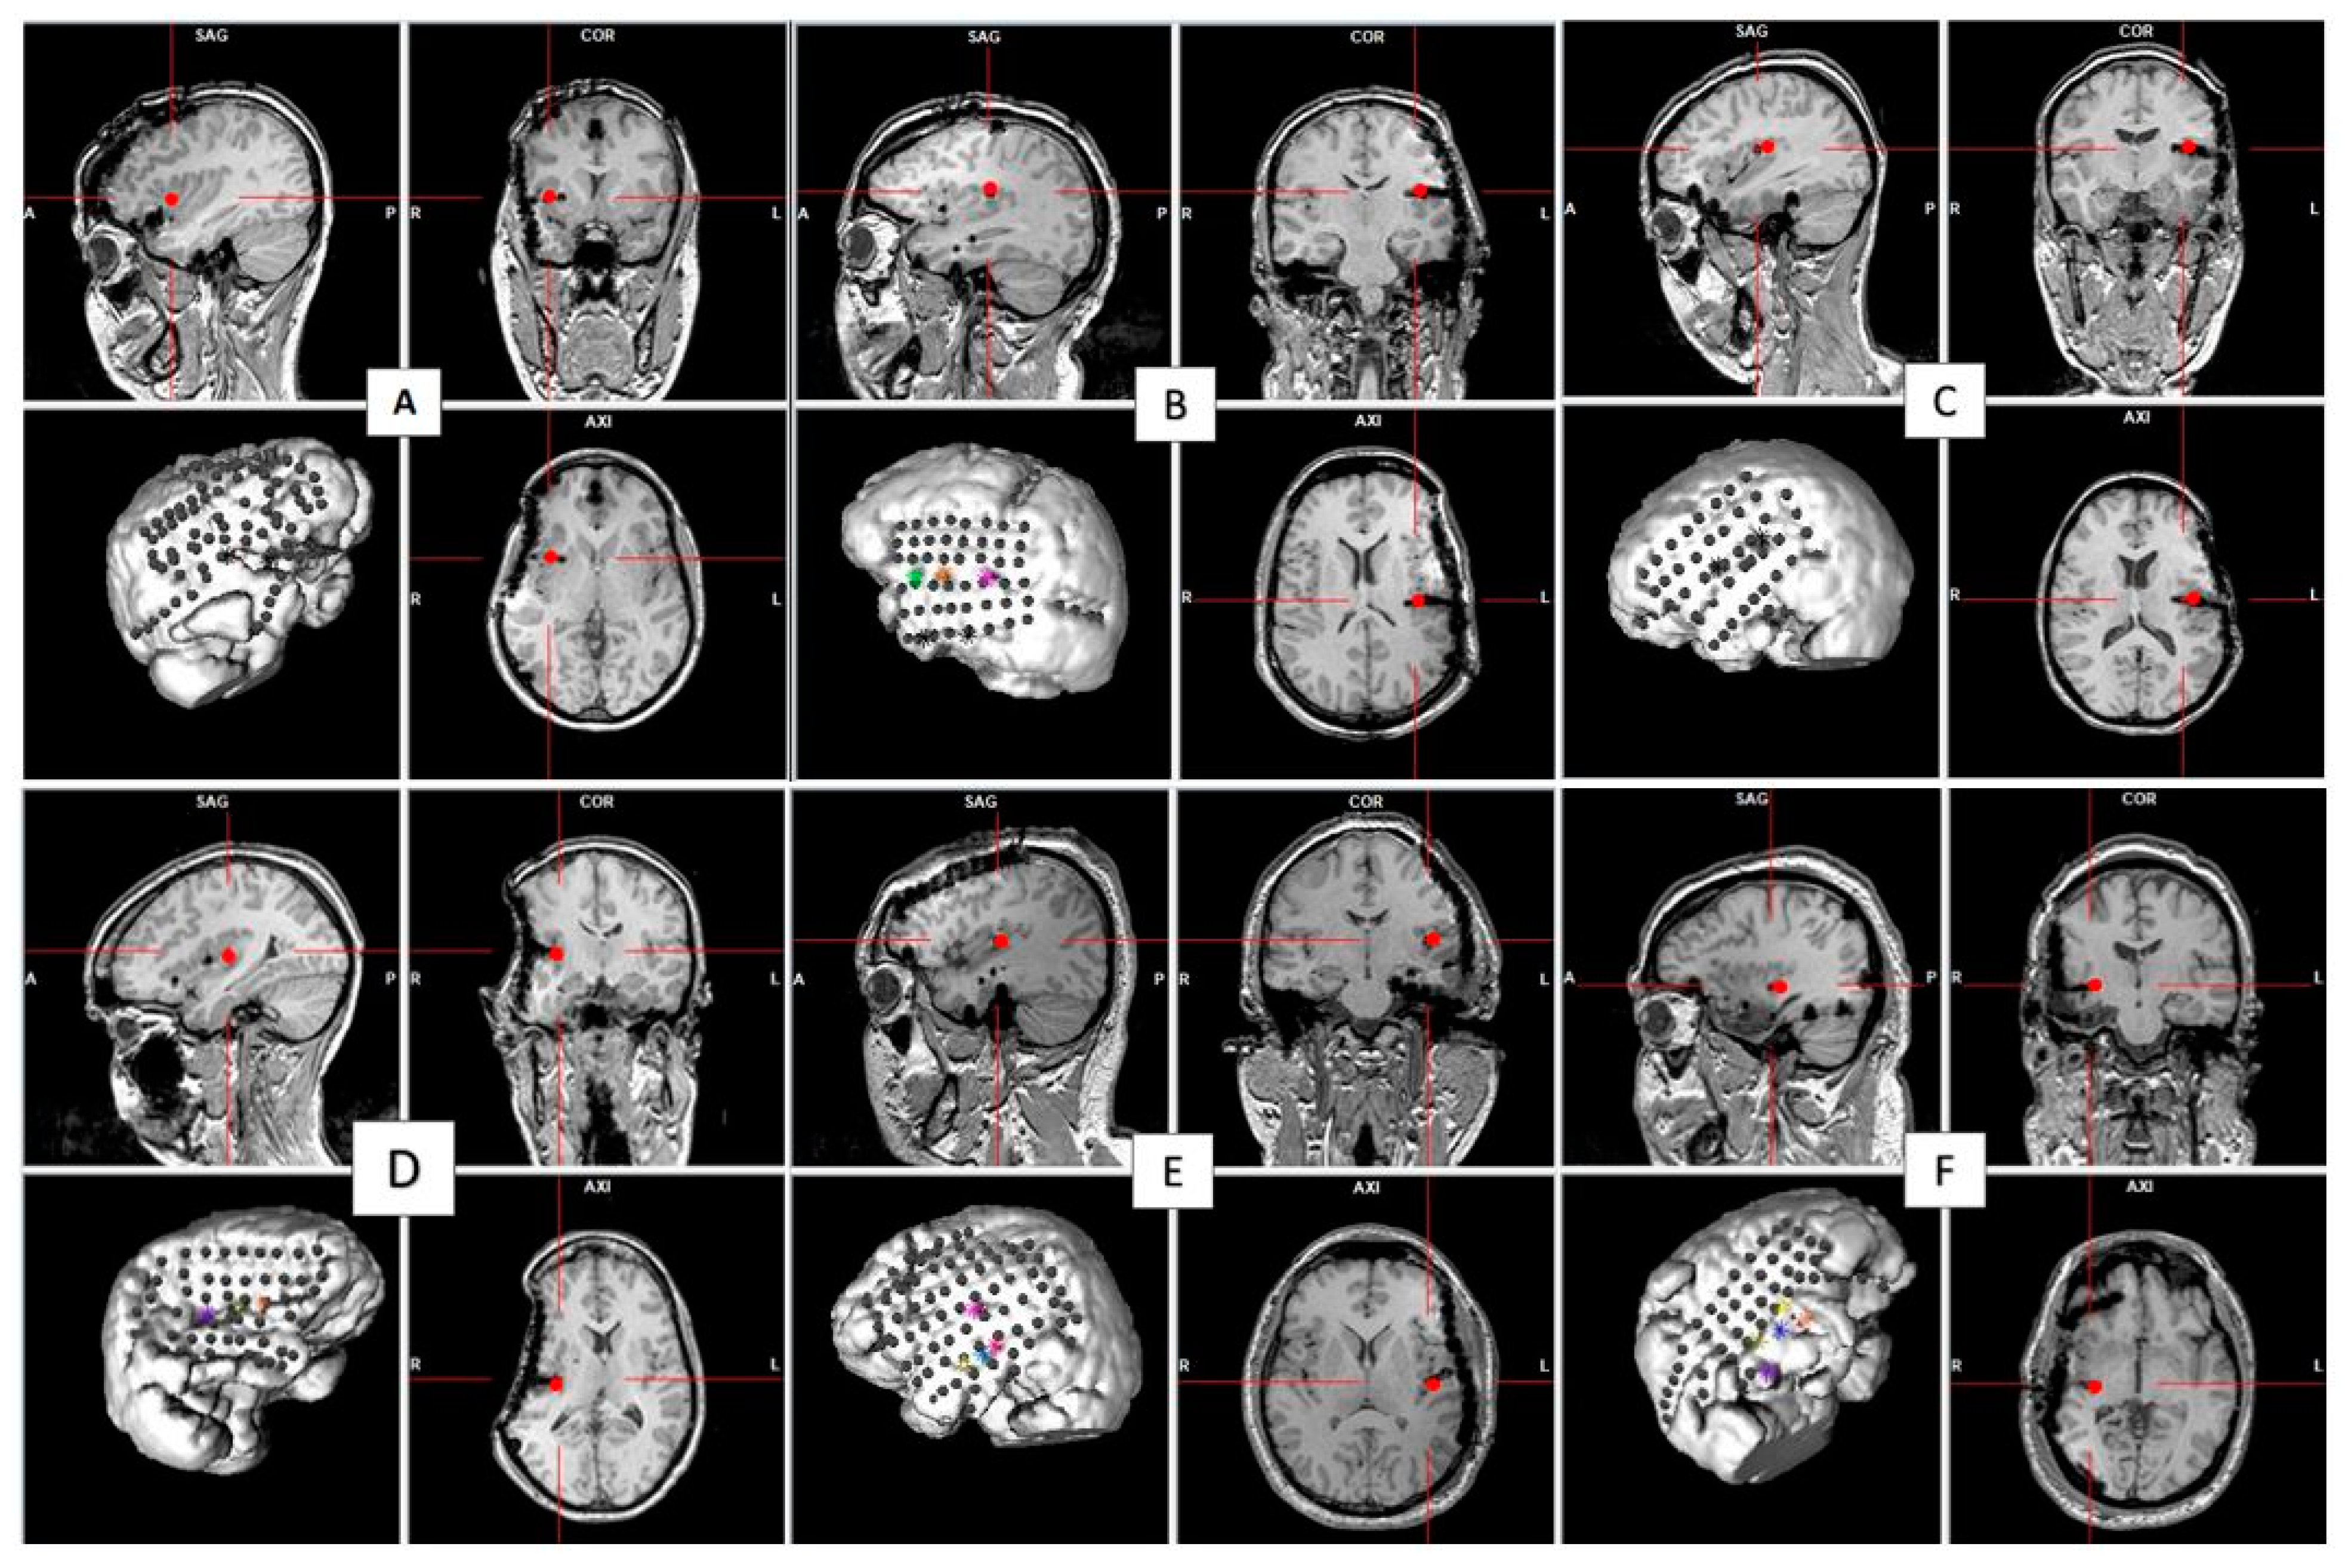

2.1. Participants and Surgical Implantation

- Group 1: HF-DBS-aINS in Patients with an Anterior Insular Epileptic Focus

- Group 2: HFS-pINS in Patients with a Posterior Insular Epileptic Focus

- Group 3: HFS-pINS in Patients with an Anterior Insular Epileptic Focus

- Group 4: HFS-pINS in Patients without an Insular Epileptic Focus